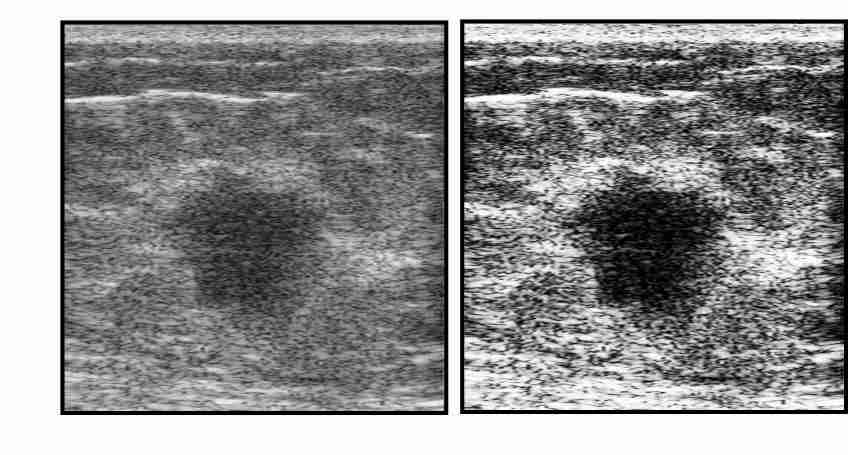

Invasive ductal carcinomas generally have fuzzy borders as a result of having invading margins. On the contrary, cancers that elicit little desmoplastic reaction (proliferation of fibroblasts) typically have clear margins, but are highly irregular in shape. We define Margin Definition as the sum of the magnitude of the gradient of on a lesion contour normalized by the sum of magnitude of on the lesion contour [33]. Although this feature uses both the lesion contour as well as a spectral parameter, we used this as a spectral feature. As is statistically well-behaved, is relatively speckle-free, and can more easily be corrected for system effects and diffraction, the midband fit image was used instead of the B-mode (envelope of RF echoes) image. Benign lesions exhibit greater value of gradient-based margin definition. Figure 3.2 shows two lesion images with sharp & fuzzy borders and shows their gradient images that are used for calculating margin definition. The lesion with sharp border gives the value of and the lesion with fuzzy border gives the value of .